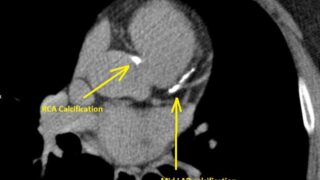

【有料級?】日米の脂質異常症(動脈硬化性疾患予防)のガイドラインを比較しながらもう一段深読みしたら日本のガイドラインが@#%&!だった件(スタチンの適切な使い方深掘りその2)

はじめにこれは仮定に仮定を積み重ねたフェルミ推定である。突拍子もない結論に見えるかもしれないが、一応ロジックの積み重ねでそこに至っている。かなり深掘りをしているので、的外れな議論はしていないはずだが、学術的な自信があるならブログではなく学術...

低リスク群へのスタチン一次予防投与は無益、または有害かもしれないという結果の論文14本+1 (スタチンの適切な使い方深掘りその1)

はじめに前回の米国の新しいガイドラインにおいてスタチンの一次予防の開始閾値は厳密にスタチンによる利益1人に必要な最小人数(NNT)、とスタチンによるNODM(new onset DM)という害の1人発症に必要な最小投与人数(NNH)が拮抗す...

知らないとマズい『LDLが高いから治療』からの卒業 〜 2026年ACC/AHA脂質ガイドラインをこれ以上わかりやすく書けないレベルで最速コソ勉

はじめに米国脂質異常症の診療ガイドライン、実に8年ぶりのアップデート(2026・3・13公開)丸1日半ぐらい、notebook LMの力を借りて、内容を把握しました。(私の「読む」という定義は何十年も前にみなさんの想像するものとは異なってい...